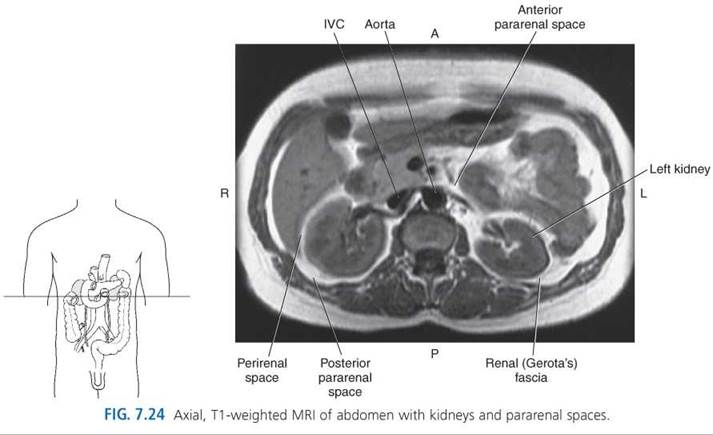

Retroperitoneal Spaces

The retroperitoneum can be divided into compartments or spaces that include the anterior and posterior pararenal spaces and left and right perirenal spaces (Fig. 7.23). The anterior pararenal space is located between the anterior surface of the renal fascia (Gerota’s fascia) and the posterior peritoneum. It contains the retroperitoneal portions of the ascending and descending colon, the pancreas, and the duodenum. The posterior pararenal space is located between the posterior renal fascia and the muscles of the posterior abdominal wall. There are no solid organs located in this space, just fat and vessels (Figs. 7.24 and 7.25). The left and right perirenal spaces are the areas located directly around the kidneys and are completely enclosed by renal fascia. The perirenal spaces contain the kidneys, adrenal glands, lymph nodes, blood vessels, and perirenal fat. The perirenal fat separates the adrenal glands from the kidneys and provides cushioning for the kidney (Fig. 7.26 and Table 7.2).